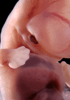

Human Embryo

Carnegie Stage 18 (44 post-ovulatory days)

Most embryos at stage 18 are approximately 44 postovulatory days old and measure 13-17 mm in length. Distinguishing criteria for this stage include cervical and lumbar flexures, distinct notching in the hand plate, the first appearance of the elbow, eyelid folds may appear in more advanced specimens, and auricular hillocks begin to form distinct parts of the external ear.